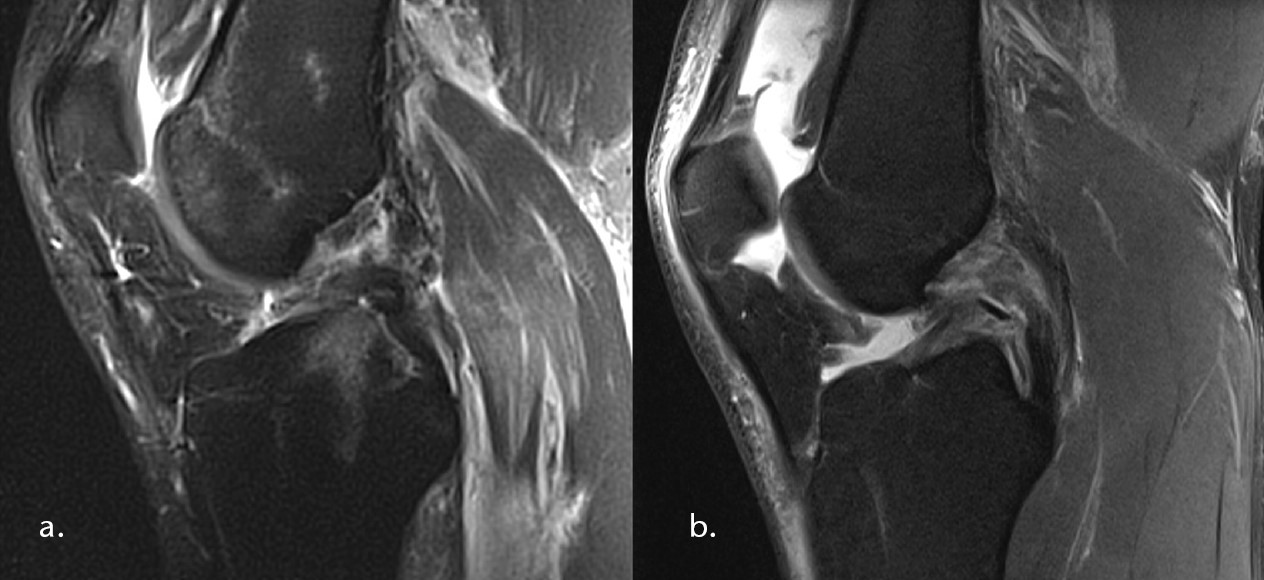

Vor allem isolierte HKB-Verletzungen eignen sich zur konservativen Behandlung. Bei zusätzlicher Verletzung z. B. des posterolateralen Ecks und somit konsekutiv erhöhter Instabilität sollte jedoch vielmehr ein operativer Therapieansatz gewählt werden1 2. In der Vergangenheit hat sich zur Einteilung weitestgehend die Hughston-Klassifikation durchgesetzt, welche isoliert nach der Laxität (instrumentell oder radiologisch gemessen) einteilt3. Grad-I- und ‑II-Verletzungen mit einer hinteren Schublade von < 10 mm sprechen für ein konservatives Vorgehen. Grad-III-Verletzungen mit einer > 10 mm Schublade suggerieren eine zusätzliche Verletzung des posterolateralen Ecks. Agolley (2017) zeigte bei konservativer Therapie dieser Grad-III-Verletzungen zwar ein hohes Return-to-Sports und einen Tegner-Score von 9, eine stabile Konsolidierung des HKBs konnte jedoch nicht erreicht werden4. Die strukturelle ligamentäre Stabilität des Gelenkes ist jedoch ein wesentlicher Faktor für die Aufrechterhaltung des Knorpelstatus. Bei Insuffizienz des HKB kommt es zu erhöhten Kontaktdrücken im medialen und patellofemoralen Kompartiment von bis zu 52 %5 6. Neben der reinen Laxizität sollte auch die Rupturmorphologie im MRT als konservatives Entscheidungskriterium mit herangezogen werden, da es Rupturformen gibt, welche nicht oder schlecht konservativ konsolidieren können. Hierzu zählen z. B. dislozierte femorale Abrisse (Abb. 1a) oder knöcherne tibiale Ausrisse mit einer Dislokation von > 6,7 mm7. Wesentlich ist der intakte Synovialschlauch als Leitstruktur für das gerissene Ligament (Abb. 1b). Auch haben sich mittlerweile minimalinvasive (arthroskopische) operative Techniken entwickelt, welche die Refixation erleichtern und gleichzeitig sehr gute klinische Ergebnisse erreichen lassen8 9. Da sowohl die konservative Behandlung als auch die operative Nachbehandlung mit einem hohen zeitlichen Aufwand verbunden sind, sollte ein „Wir versuchen es mal“ möglichst vermieden werden. Die frühzeitige Einleitung der adäquaten Versorgung, sowohl konservativ als auch operativ, ist essentiell wichtig.